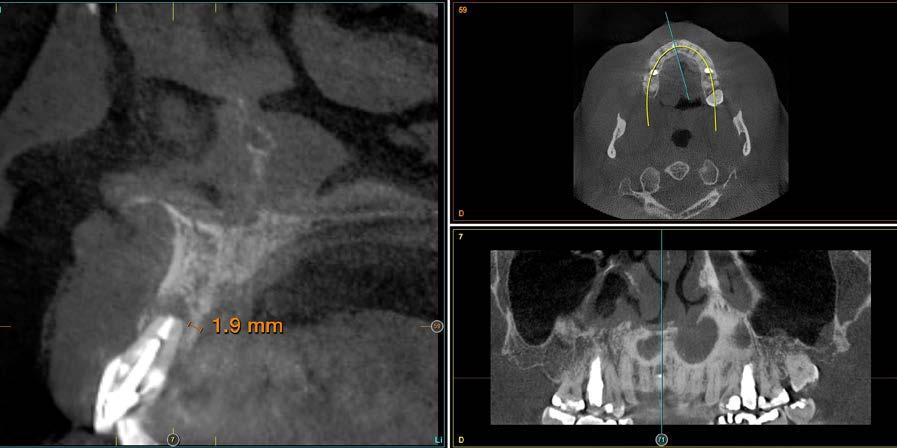

Para evitar que tras la cicatrización del alveolo se produzca un defecto que genere un compromiso estético en la zona vestibular una de las estrategias más empleadas es la colocación del implante postextracción inmediata ligeramente palatinizado. La variación de la posición del

implante hacia palatino para evitar la proximidad a la tabla vestibular implica que en muchos casos entre el implante y la tabla ósea vestibular se genere un espacio conocido como “gap” en el implante postextracción inmediata. Este espacio en ocasiones debe ser rellenado para evitar el colapso posterior estableciéndose como norma general que en aquellos casos en los que el grosor de la tabla vestibular oscile entre 1 y 2 mm y el espacio del gap es menor de 2 mm la capacidad regeneradora propia del alveolo haría que no fuese necesario el relleno del gap con ningún tipo de material para que se produjese la regeneración ósea en el mismo.13 Otros casos en los que la cortical sea de menor grosor o el gap de mayor distancia (o la combinación de ambos factores) debe ser rellenado el espacio con un biomaterial que permita la regeneración más favorable del defecto.13,14 Dentro de los materiales de relleno que pueden utilizarse, en la literatura internacional tenemos: hueso autólogo, hueso desmineralizado desecado y congelado, hueso mineralizado desecado y congelado, xenoinjerto, fosfato tricálcico y plasma rico en factores de crecimiento.15,16 El empleo de PRGF-Endoret para el manejo de este gap en el implante postextracción es un enfoque biológico y totalmente autólogo basado en las propias proteínas y señales celulares del paciente que nos garantiza buenos resultados a largo plazo, según las referencias publicadas en la literatura internacional donde se ha confirmado el potencial

Figura 1. Radiografía panorámica inicial del caso donde observamos el defecto óseo alrededor del ápice de la pieza 11.

El defecto circunferencial recubre todo el ápice y hace que la tabla vestibular se encuentre ausente en prácticamente toda la superficie radicular además de dejar un remanente palatino de menos de 2 mm.

radiografía panorámica inicial para el diagnóstico nos aporta una imagen radiolucida entorno al ápice del diente en posición 11 ( Figura 1 ). Para conocer mejor el alcance de la lesión y las opciones terapéuticas de las que disponemos se lleva a cabo un cone-beam en el que se puede objetivar de forma precisa el defecto apical al diente. Este defecto es circunferencial y está dejando una reabsorción casi completa de la tabla ósea vestibular y parcial de la palatina, con un grosor de 1.9 mm, como vemos en el corte seccional (Figura 2). Si observamos la medida total en la zona media del incisivo dentral, necesitamos cubrir una anchura aproximada de 8 mm por lo que el implante que coloquemos irremediablemente dejará un gap, que según los protocolos quedará en vestibular. Utilizando una plataforma estándar de 4.1 mm el gap a rellenar será prácticamente de 4 mm según las medidas que nos

Figura 2. Corte seccional del cone-beam

arroja el cone-beam de planificación. Utilizaremos además un implante de longitud mayor que la que se emplearía para un incisivo central en una zona edéntula, para lograr un anclaje apical que nos dé la estabilidad necesaria en la colocación del implante y

nos permita la carga inmediata posterior. En este caso 11.5 mm (Figura 3 y 4).Una vez diagnosticado el caso de forma correcta con las imágenes del cone-beam iniciamos la fase quirúrgica. Realizamos la exodoncia del diente 11 con el menor trauma